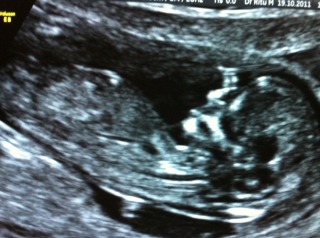

Been told both, any wise ones keen for a guess?

that looks like a girl

we arent seeing all of the nub, esp the end is missing which could be misleading, I would ever so slightly lean girl based on this shot. Do you have any more?

right at the base of the baby there is a white fleck, below it a black parallel line, and that's roughly where the nub is on a baby

Girl, based on angle of nub

Girl, based on nub and skull